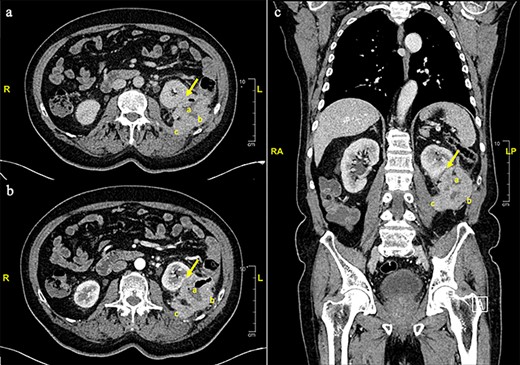

This is a 75-year-old man with a past medical history of diabetes mellitus and hypertension. He had a history of 6 months of an intense left flank pain. Physical exam was unremarkable. An abdominal ultrasound described a left renal mass. Computed tomography (CT) showed a 7.3 × 5 cm mass in the descending colon infiltrating the left kidney, iliopsoas muscle and retroperitoneum. No distant metastases were observed (Fig. 1).

Contrast enhanced thorax, abdomen and pelvis computed tomography scan. a. Axial plane, non-contrast phase. s. Axial plane, venous phase. c. Coronal plane. An eccentric parietal thickening, sized 7.3 × 5 cm. With a cavitated center was observed (a), anteriorly displacing the left kidney with no clear cleavage plane in its inferior third (arrow). A loss of cleavage plane with the posterior-lateral left abdominal wall (b) and the psoas-iliac muscle (c) was also described.